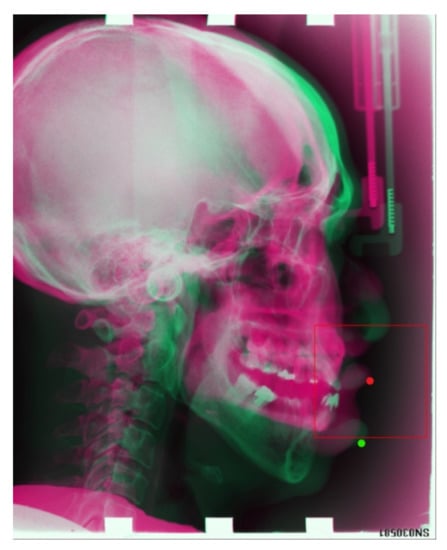

At first, we try to input all the X-ray images to predict all 19 landmarks simultaneously. We performed conventional data augmentation on training data, such as rotation, cropping, and so on. However, the result is not satisfying; although the location of all the landmarks is very similar to the ground truth, the predicted results are very far from the ground-truth result, as presented in Figure 11.

Figure 11. Green points: predicted landmarks’ locations. Red points: ground-truth locations of landmarks. We can see the result is not satisfying at all.